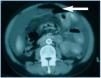

In spite of antibiotic treatment, the patient remained clinically symptomatic. In an abdominal Computerized Axial Tomography (CAT), hydropneumoperitoneum in small quantity was visible as were cysts in both ovaries, the left side larger in size (figure 1).

Figure 1.